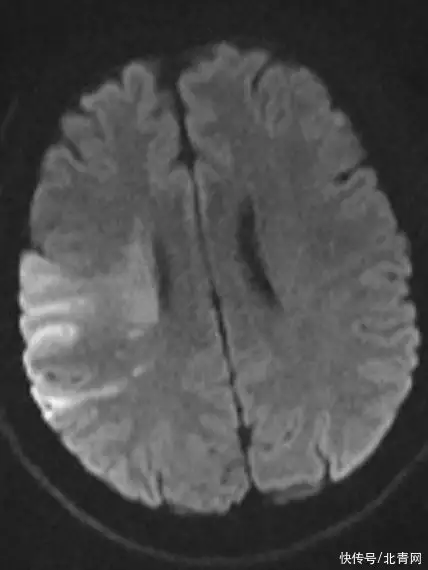

阿杰被送到医院后,负责接诊的神经内科介入组的医生凭借多年的临床经验,判断阿杰可能是急性脑梗死,也就是我们常说的脑中风!于是,医院立即为阿杰开通绿色通道行了头颅CT及头颅MRI检查检查结果出来后,阿杰被诊断为突发急性脑梗,也就是脑中风。

左图:梗死的脑组织

右图:颈动脉夹层为何33岁小伙会突然脑中风?与阿杰沟通后,医生判断“罪魁祸首”很有可能是颈部按摩为什么颈部按摩会导致脑中风?由于颈部没有骨头保护、很脆弱当用力去按压颈部肌肉时,如果挤压到了动脉血管,则可能出现血管内膜层的撕裂,血液侵入血管管壁内导至壁内血肿,形成动脉夹层。